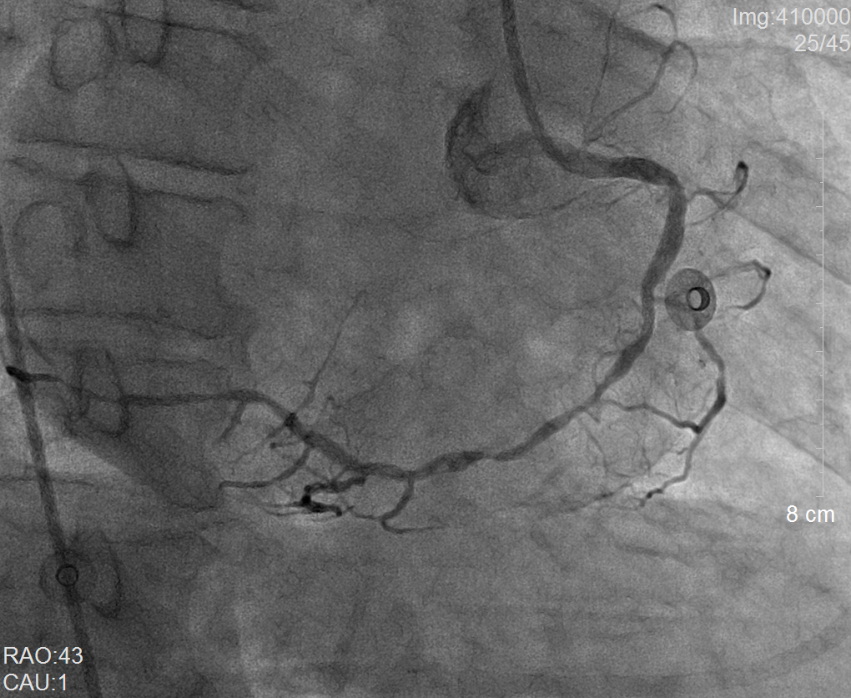

术前冠脉造影提示右冠状动脉弥漫性病变                 术后冠脉造影提示右冠状动脉血流通畅

在开通“犯罪血管”后,林先生出现应激性溃疡,呕吐大量鲜血,被紧急送至心内科重症监护病房(CCU)抢救。消化内科郑玮玮医师为林先生在床边行急诊消化内镜并在内镜下止血,这才停止了呕血。同时,林先生还合并严重的肺部感染和心衰,经过呼吸内科陈公平主任医师多次精准调整抗生素和心内科重症医学团队的精细救治,术后第11天,患者肺部感染和心衰就得到了良好的控制,并于1月29日进行了第二次PCI治疗。距急诊手术后第13天,林先生病情稳定,顺利出院。